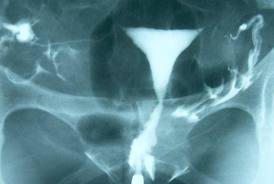

Kontrast bir madde ile rahim içi boşluğun, tüplerin ve pelvisin değerlendirildiği bir radyolojik yöntemdir. Halk arasında boyalı rahim filmi, kanal filmi olarak da bilinir.

HSG, aslında özel bir röntgen çekim işlemidir. Kadın jinekolojik pozisyonda röntgen masasına yatırılır. Antiseptik solüsyonla dış genital organ ve vajina dezenfeksiyonunu takiben serviks özel bir aletle sabitlenir. Servikal kanaldan içeri itilen özel bir kanül vasıtası ile kontrast madde rahim içine enjekte edilir. İşlem birkaç aşamada gerçekleştirilir. Enjekte edilen madde miktarı ve enjeksiyon basıncı ayarlanarak kontrast maddenin rahim içini doldurması, tüplerden geçişi, pelvis (alt karın boşluğu) içinde dağılışı, filmler çekilerek görüntülenir. Daha sonra bu filmler incelenerek rahim içinde bir bölme, polip veya myom varlığı, rahim yapısı, tüplerin açık olup olmadığı, tüplerin uç kısmının alt karın boşluğuna açılıp açılmadığına bakılır.